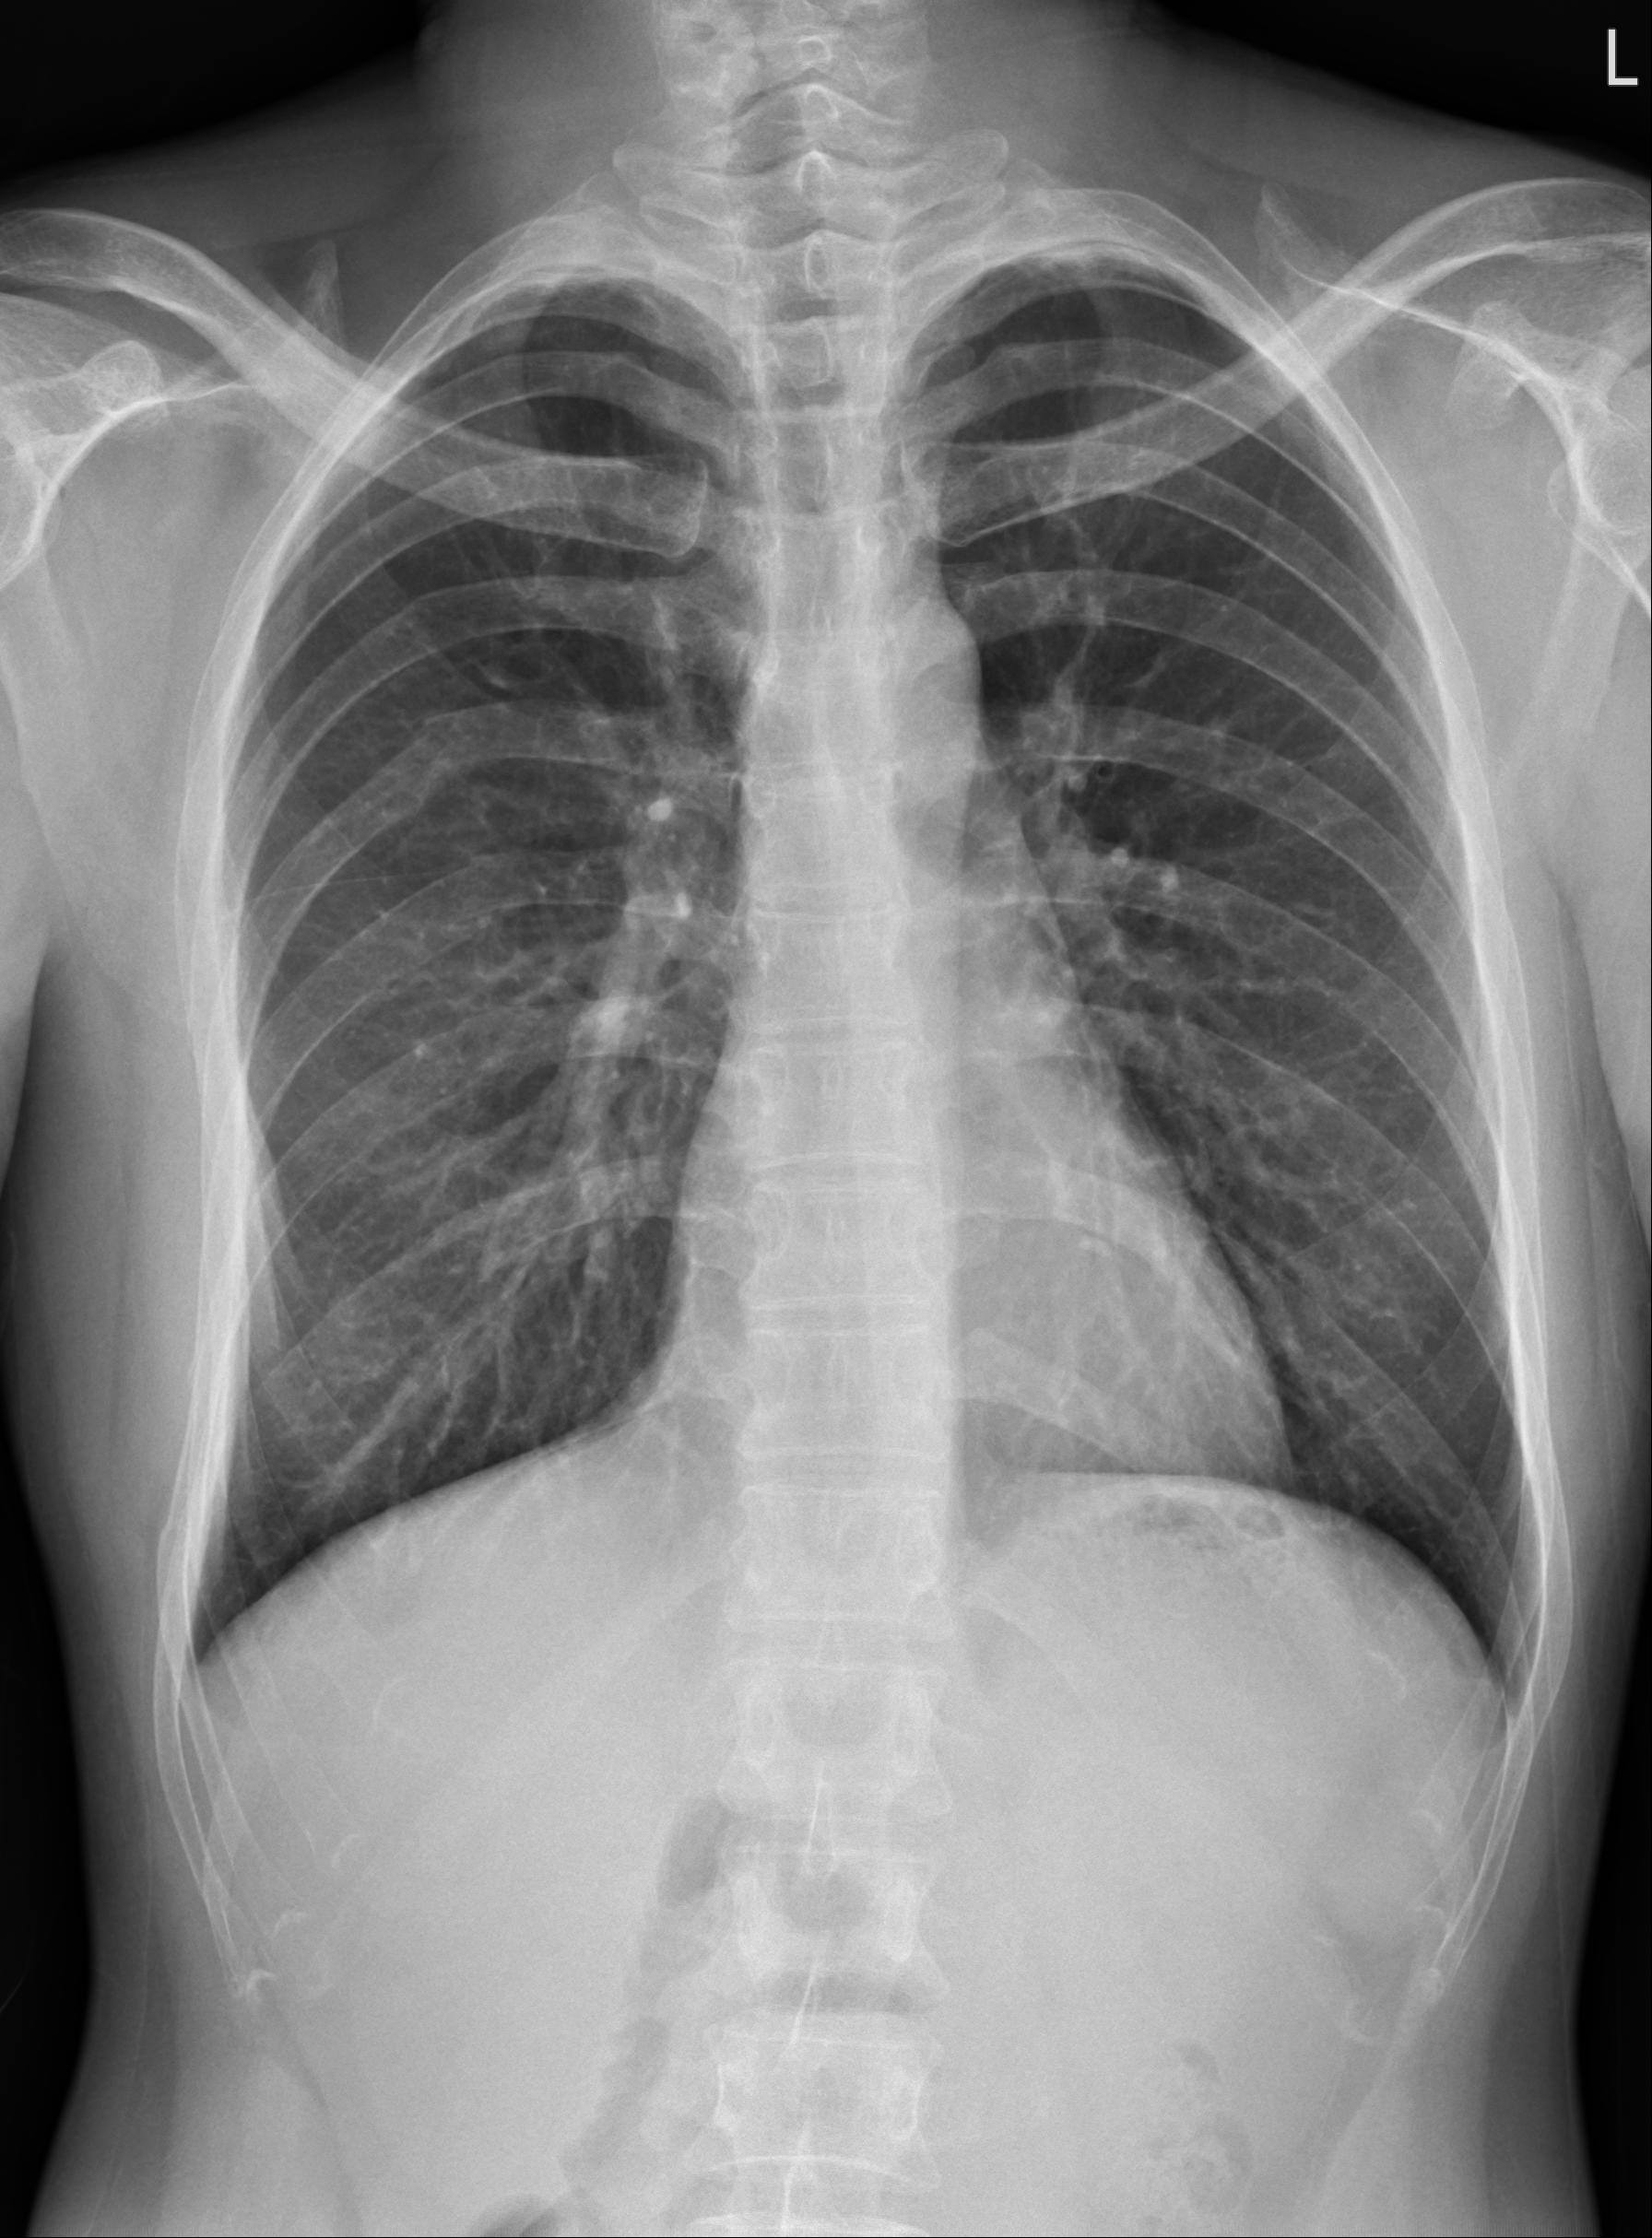

年輕男性,機車車禍,除四肢多處擦傷,還主訴右側胸痛

生命徵象穩定,無呼吸困難,但有明顯壓痛。

CXR可見右側胸部多處肋骨骨折。